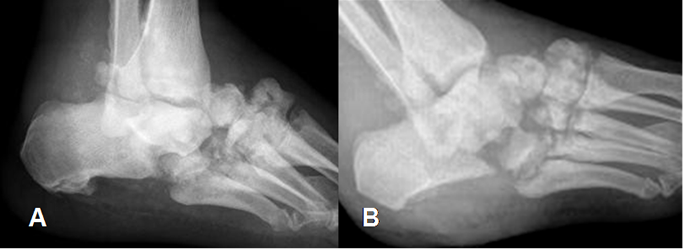

Fig 46. Artropatía neuropática. Patrón atrófico.

A: Rx lateral del tobillo y B: Rx oblicua del pie. Alteración osea con remodelación del talo, el calcáneo y los huesos del medio pie.